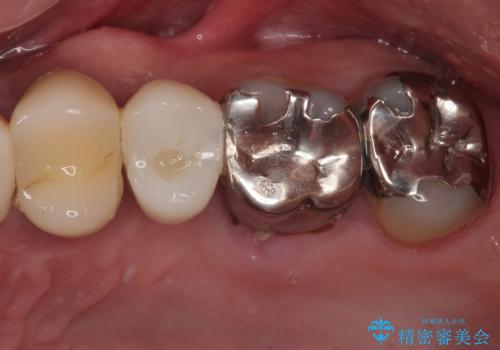

抜歯と同日にインプラントを埋入し、さらに仮歯まで装着するため、治療当日から見た目と噛む機能の回復が可能です。治療期間中も審美性と日常生活の快適さを維持できます。

抜歯即時インプラント後、治癒期間を経て、約3か月でセラミックによる最終補綴が完了しました。